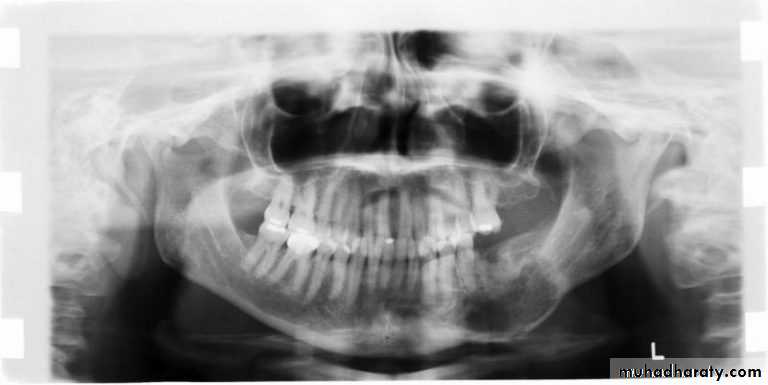

Radiographical appearance ;

It is possible to see a patient with acute osteomyelitis that has a normal-appearing orthopantomogram. However, one can often see the appearance of "moth-eaten" bone or sequestrum of bone, which is the classic appearance of osteomyelitis.14

Computerized tomography (CT) scans have become the standard in evaluating maxillofacial pathology such as osteomyelitis. its sensitive in late stage when 30%-50% of the bone demineralized.